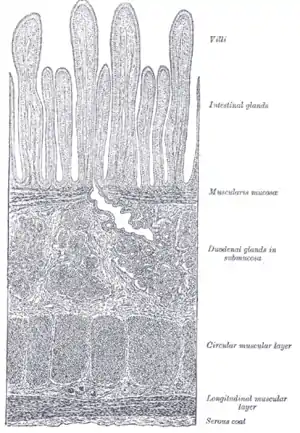

Section of duodenum of cat. X 60. (Muscularis mucosae labeled at right, third from the top.) | |

| Muscularis mucosae | |

The lamina muscularis mucosae (or muscularis mucosae) is a thin layer (lamina) of muscle of the gastrointestinal tract, located outside the lamina propria, and separating it from the submucosa. It is present in a continuous fashion from the esophagus to the upper rectum (the exact nomenclature of the rectum's muscle layers is still being debated). A discontinuous muscularis mucosae–like muscle layer is present in the urinary tract, from the renal pelvis to the bladder; as it is discontinuous, it should not be regarded as a true muscularis mucosae.

The muscularis mucosae is composed of several thin layers of smooth muscle fibers oriented in different ways which keep the mucosal surface and underlying glands in a constant state of gentle agitation to expel contents of glandular crypts and enhance contact between epithelium and the contents of the lumen.